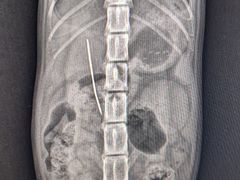

• -爱诺耐芙动物医院(万博店)

GQGQ | 23-10-07

报错